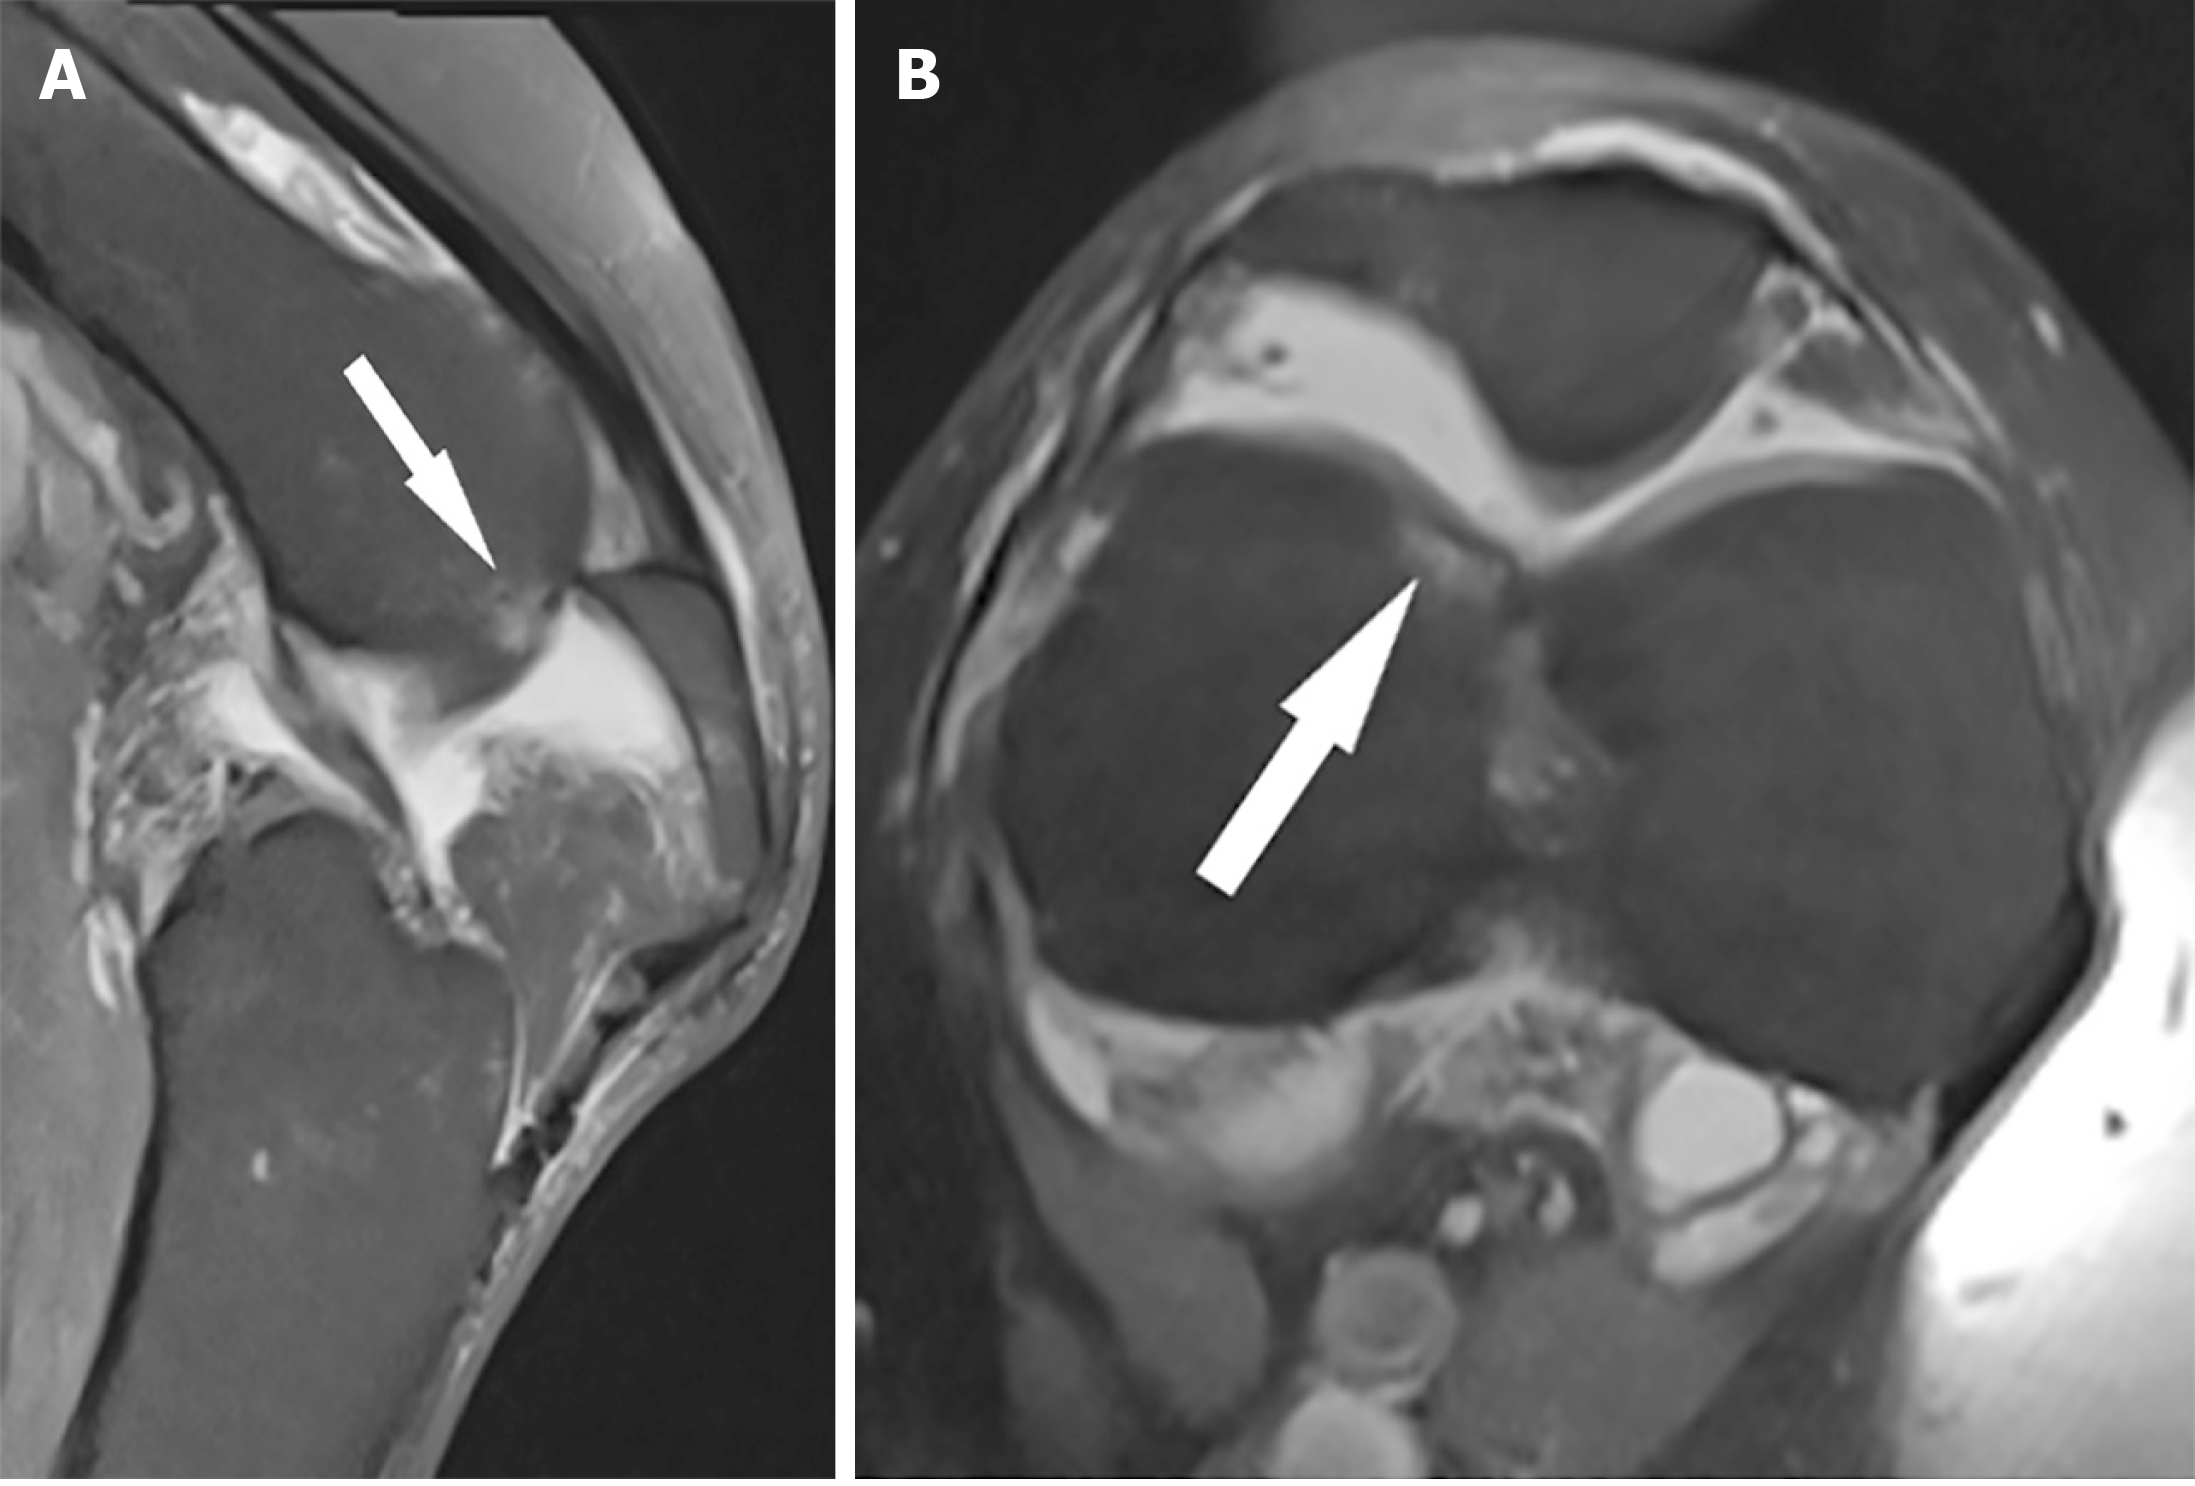

Figure 4 Progress X-rays at 9 months: Interval healing of the fracture at the medial margin of the femoral trochlear, where the fracture is not visualised and alignment appears anatomical.

This is best demonstrated on the skyline projection (bottom right). Background advanced patellofemoral compartment degenerative change is present.